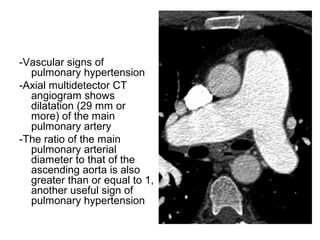

-Vascular signs of

pulmonary hypertension

-Axial multidetector CT

angiogram shows

dilatation (29 mm or

more) of the main

pulmonary artery

-The ratio of the main

pulmonary arterial

diameter to that of the

ascending aorta is also

greater than or equal to 1,

another useful sign of